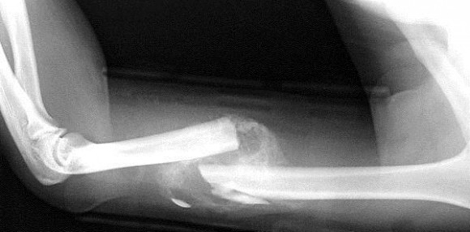

In diesem Beitrag geht es um das schmerzhafte Thema Knochenbrüche und wie man die Knochen auf natürlichem Wege zu einem schnelleren Heilprozess anregen kann.

Unser heutiger Lebenswandel und gefährliche Sportarten wie Motorcross fahren, dirtbiken oder snowboarden führen dazu, dass wir uns öfter Knochen brechen und uns verletzen. Es ist sehr wichtig als erstes einen Arzt aufzusuchen, der die Knochen wieder richtet und so gewährt, dass sie richtig zusammenwachsen. Allerdings wäre es unklug darauf zu vertrauen, dass unser Körper die ganze Regenerationsarbeit schon selber macht. Natürlich ein junger und gesunder Körper wird mit einem Knochenbruch keine Probleme haben, aber nicht jeder ist gesund und hat alle Stoffe im Körper die es für diese Knochenregeneration braucht.